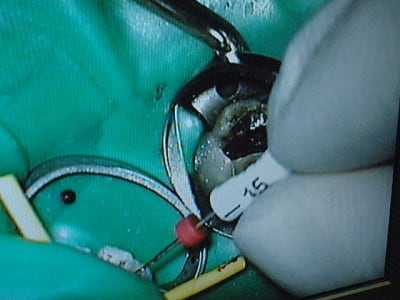

Bon repas, je digère...lui déguste endos 21/11 avec digue....

D'abord, finissons le cas du matin

photos :

pas de digue sur les radios....il a profité d'une pause pipi pour faire la radio...

traitement 1h40

Première endo, pfff, pas facile, une 26... patiente très patiente, parce que, comme il l'a subtilement fait comprendre, j'ai été leeeeeeeennnnt... mais comprenez moi, je n'étais pas chez moi ! J'aurais eu l'air de quoi, je savais qu'il posterait les radios !

Alors, le croscope, c'est vrai, on voit le bout du tunnel avec... plus les différents inserts ultrasonores du Sbirounet, franchement, on a pas l'impression de faire le meme métier avec... c'est très étonnant, et très nouveau (mouarf le jeunot). Alors le midi on a été au resto, il a insisté pour payer, alors, bon, je voulais pas le mettre mal devant ces patients (visiblement la patronne était une connaissance), je l'ai laissé jouer le prince... (merci !)

Le microscope est un outil impressionant, que je qualifierais d'outil plaisir, outil car utilité démontrée en cas de fracture canalaire, en cas de recherche du fameux mv2 (pas trouvé moi, ce matin...) mais... plaisir car on peut sûrement faire aussi bien sans... mais c'est moins rigolo et on se casse le dos.